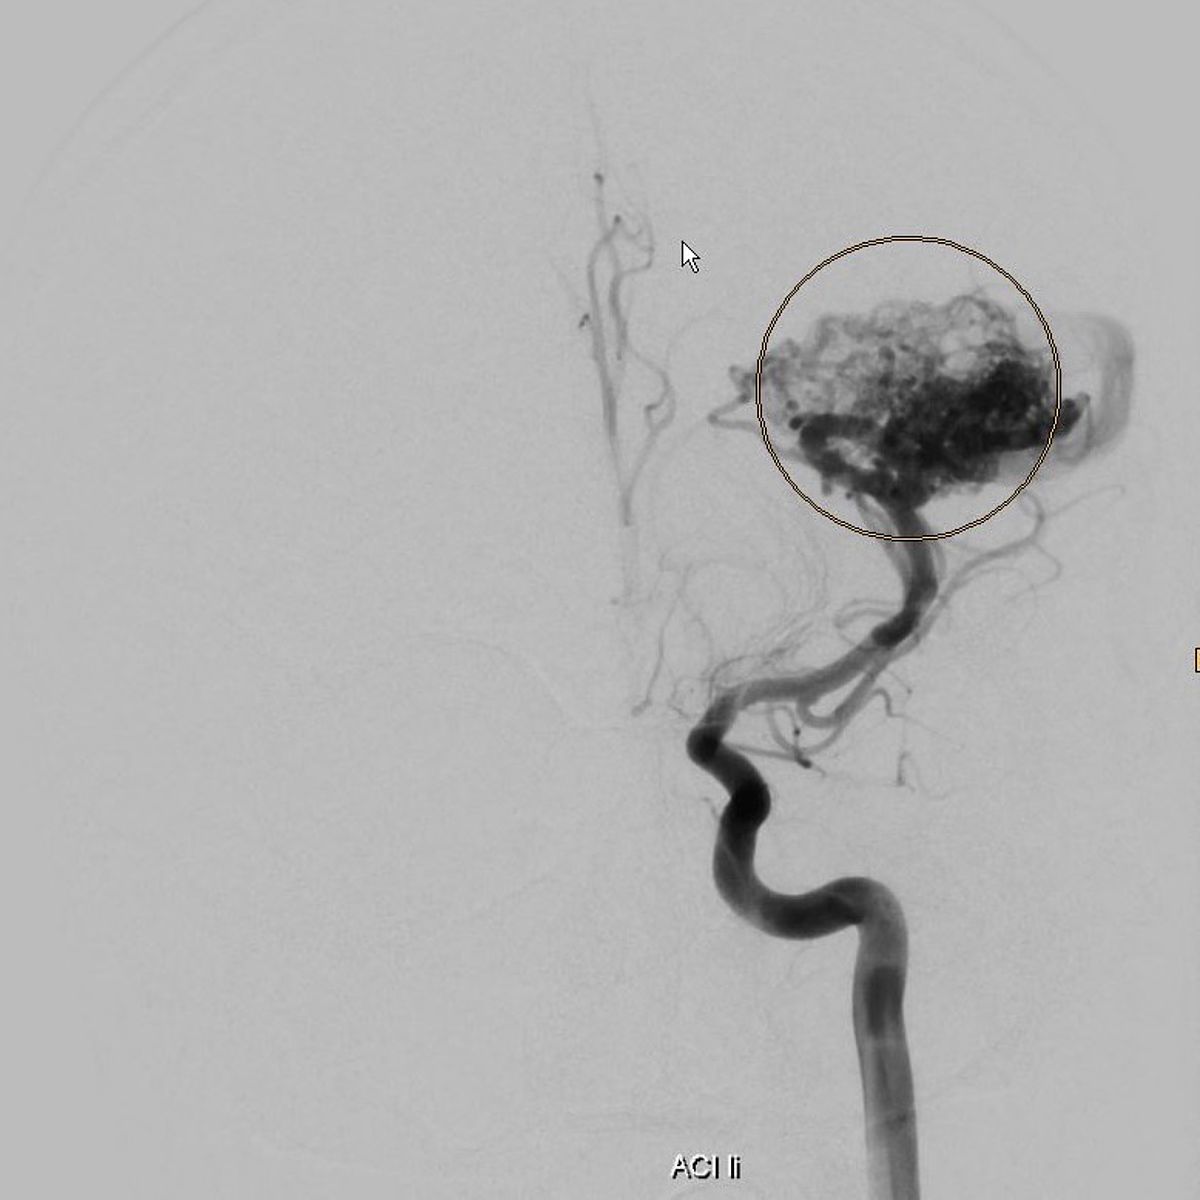

Gefäßmissbildungen und -tumore können zu Blutungen führen, aufgrund ihrer Größe lokale Probleme verursachen oder auch nur rein ästhetisch störend sein.

Die Neuroradiologie ist bei der Diagnostik solcher Gefäßveränderungen mit Computertomographie, Kernspintomographie und vor allem der Angiographie gefragt.

Im Rahmen der interventionellen Therapie sind endovaskuläre und perkutane Injektionen mit verödenden Substanzen, Gewebe- und Gefäßkleber möglich.